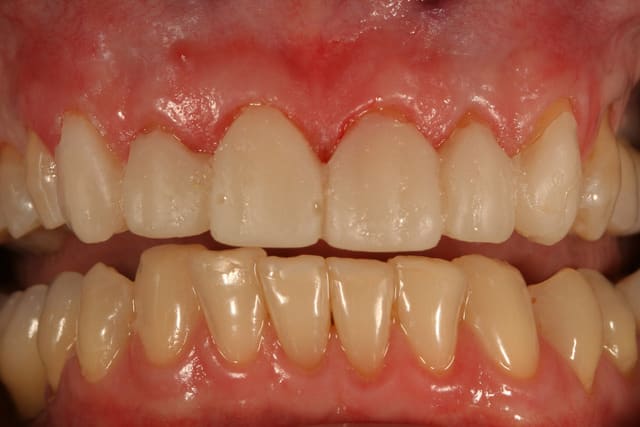

essayage, et comme on peut le voir sur la première photo, c'est bizarement long par rapport au provisoire ...

pourtant le prothésiste avait un alginate des mocks-up

j'ai mis du sealtemp et essayé tout ça, c'est trop long

par contre, je me dis que je suis resté trop supra-gingival sur mes préparations, ça se voit trop, même si la patiente découvre peu, elle découvre un peu et j'aurais du aller plus juxta.

voilà le resultat collé

je suis resté trop supragingival, mais la patiente est très contente (ouf, c'est l'essentiel !)

elle a sa gouttière pour la nuit